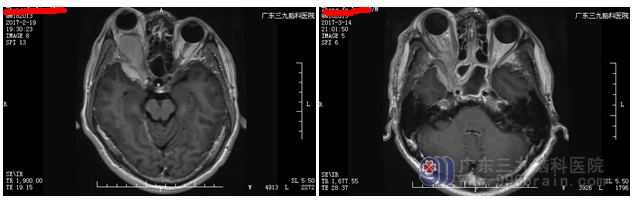

张姓男子,40岁,前3年出现无明显诱因右眼突出症状,未予重视。后上述症状逐渐加重,右眼球后部存在压迫感。就诊当地医院,行头颅CT及MR检查均提示右侧眼眶及颅内占位性病变,为求进一步治疗,遂来我院就诊。

入院经专家会诊后反复讨论,制定出手术治疗方案,因为肿瘤组织侵犯到视神经,为了最大程度保护视神经,不影响病人康复后生活,所以制订两个计划:行术中冰冻,如结果为良性,则保留视神经;如为恶性肿瘤,则切除视神经。手术由神经外二科主任林涛医师完成,行全麻下右侧蝶骨脊旁脑膜瘤及右侧眼眶内脑膜瘤切除术+颅底重建术。术后病理为脑膜瘤合体细胞型WHOI级。术后患者恢复良好。